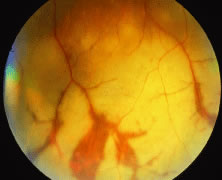

The ARN patient typically presents with progressive visual blurring in one or both eyes occurring over several weeks. These patients often are initially treated with corticosteroids, antitoxoplasmosis drugs, and other medications before arriving at the correct diagnosis. Examination reveals a prominent anterior uveitis that may be granulomatous or nongranulomatous (Fig. 1). Inflammatory signs may be prominent and cause severe pain (Fig. 2). The uveitis may be diffuse and so severe that it causes proptosis. These signs, and the diffuse vitreitis that makes the view of the retina difficult, may contribute to the high degree of delayed and/or misdiagnosis that occurs in the early stages of the disease. Significant vitreous cellular infiltration is seen in the presence of retinitis that is manifest by opacification of the retina, often most prominently in the periphery. Posterior pole involvement may include retinitis, as well as inflammation of the optic nerve head. Optic neuropathy might be the first sign of ARN with subsequent development of other retinal manifestations.8 Ultrasonography and computed tomography (CT) might be helpful in cases of ARN associated with optic nerve edema revealing enlargement of the optic nerve sheath.9 Even in ARN patients who are not immunocompromised and who have no clinical evidence of encephalitis, magnetic resonance imaging of selected cases has shown lesions of the lateral geniculate, optic tracts, and chiasma, which suggests that the virus spreads through the central nervous system (CNS) by axoplasmic transport from the retinal ganglion cells.10 A secondary retinal vasculitis is common, often accompanied by a mild number of retinal hemorrhages. Days to weeks after onset of the infection, the discrete peripheral lesions typically coalesce into a white or yellow ring of infected retina, and the associated vasculature is obliterated (Fig. 3). Necrotic retina desquamates into the vitreous resulting in vitreous sheets.3,6 Eventually, most untreated eyes can be expected to develop retinal detachment resulting from development of multiple full-thickness retinal breaks accompanied by traction or exudation.11 Giant retinal pigment epithelial tears have also been reported.12

Fig. 3. Confluent peripheral retinitis seen in acute retinal necrosis. The perivascular lucent areas with some evidence of hemorrhage are typical of this disease.